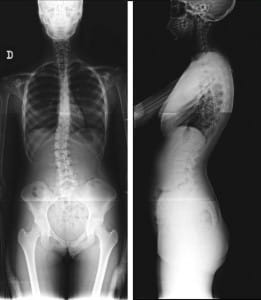

El espinograma o espinografía es un estudio de rayos X que abarca toda la columna vertebral o espina (desde el cuello y hasta la pelvis), obteniendo así una vista panorámica de toda la columna.

Se realiza en posición de frente o de perfil. Se muestra toda la imagen en una sola placa.

Este sencillo estudio radiográfico nos permite visualizar y evaluar la alineación de todas las vértebras, las que deben estar siempre bien alineadas desde arriba hacia abajo, (igual a como cae el hilo de la plomada del albañil), en la visión de frente y en la visión de perfil se controlan las curvaturas que deben ser cervical y lumbar en lordosis (concavidad posterior) y dorsal y lumbar en cifosis (concavidad anterior).

Es pedido por el profesional médico frecuentemente para pacientes traumatológicos con diagnósticos por ejemplo de escoliosis, acortamiento de miembros inferiores, etc.

Ver caso real de Cifoescoliosis juvenil.